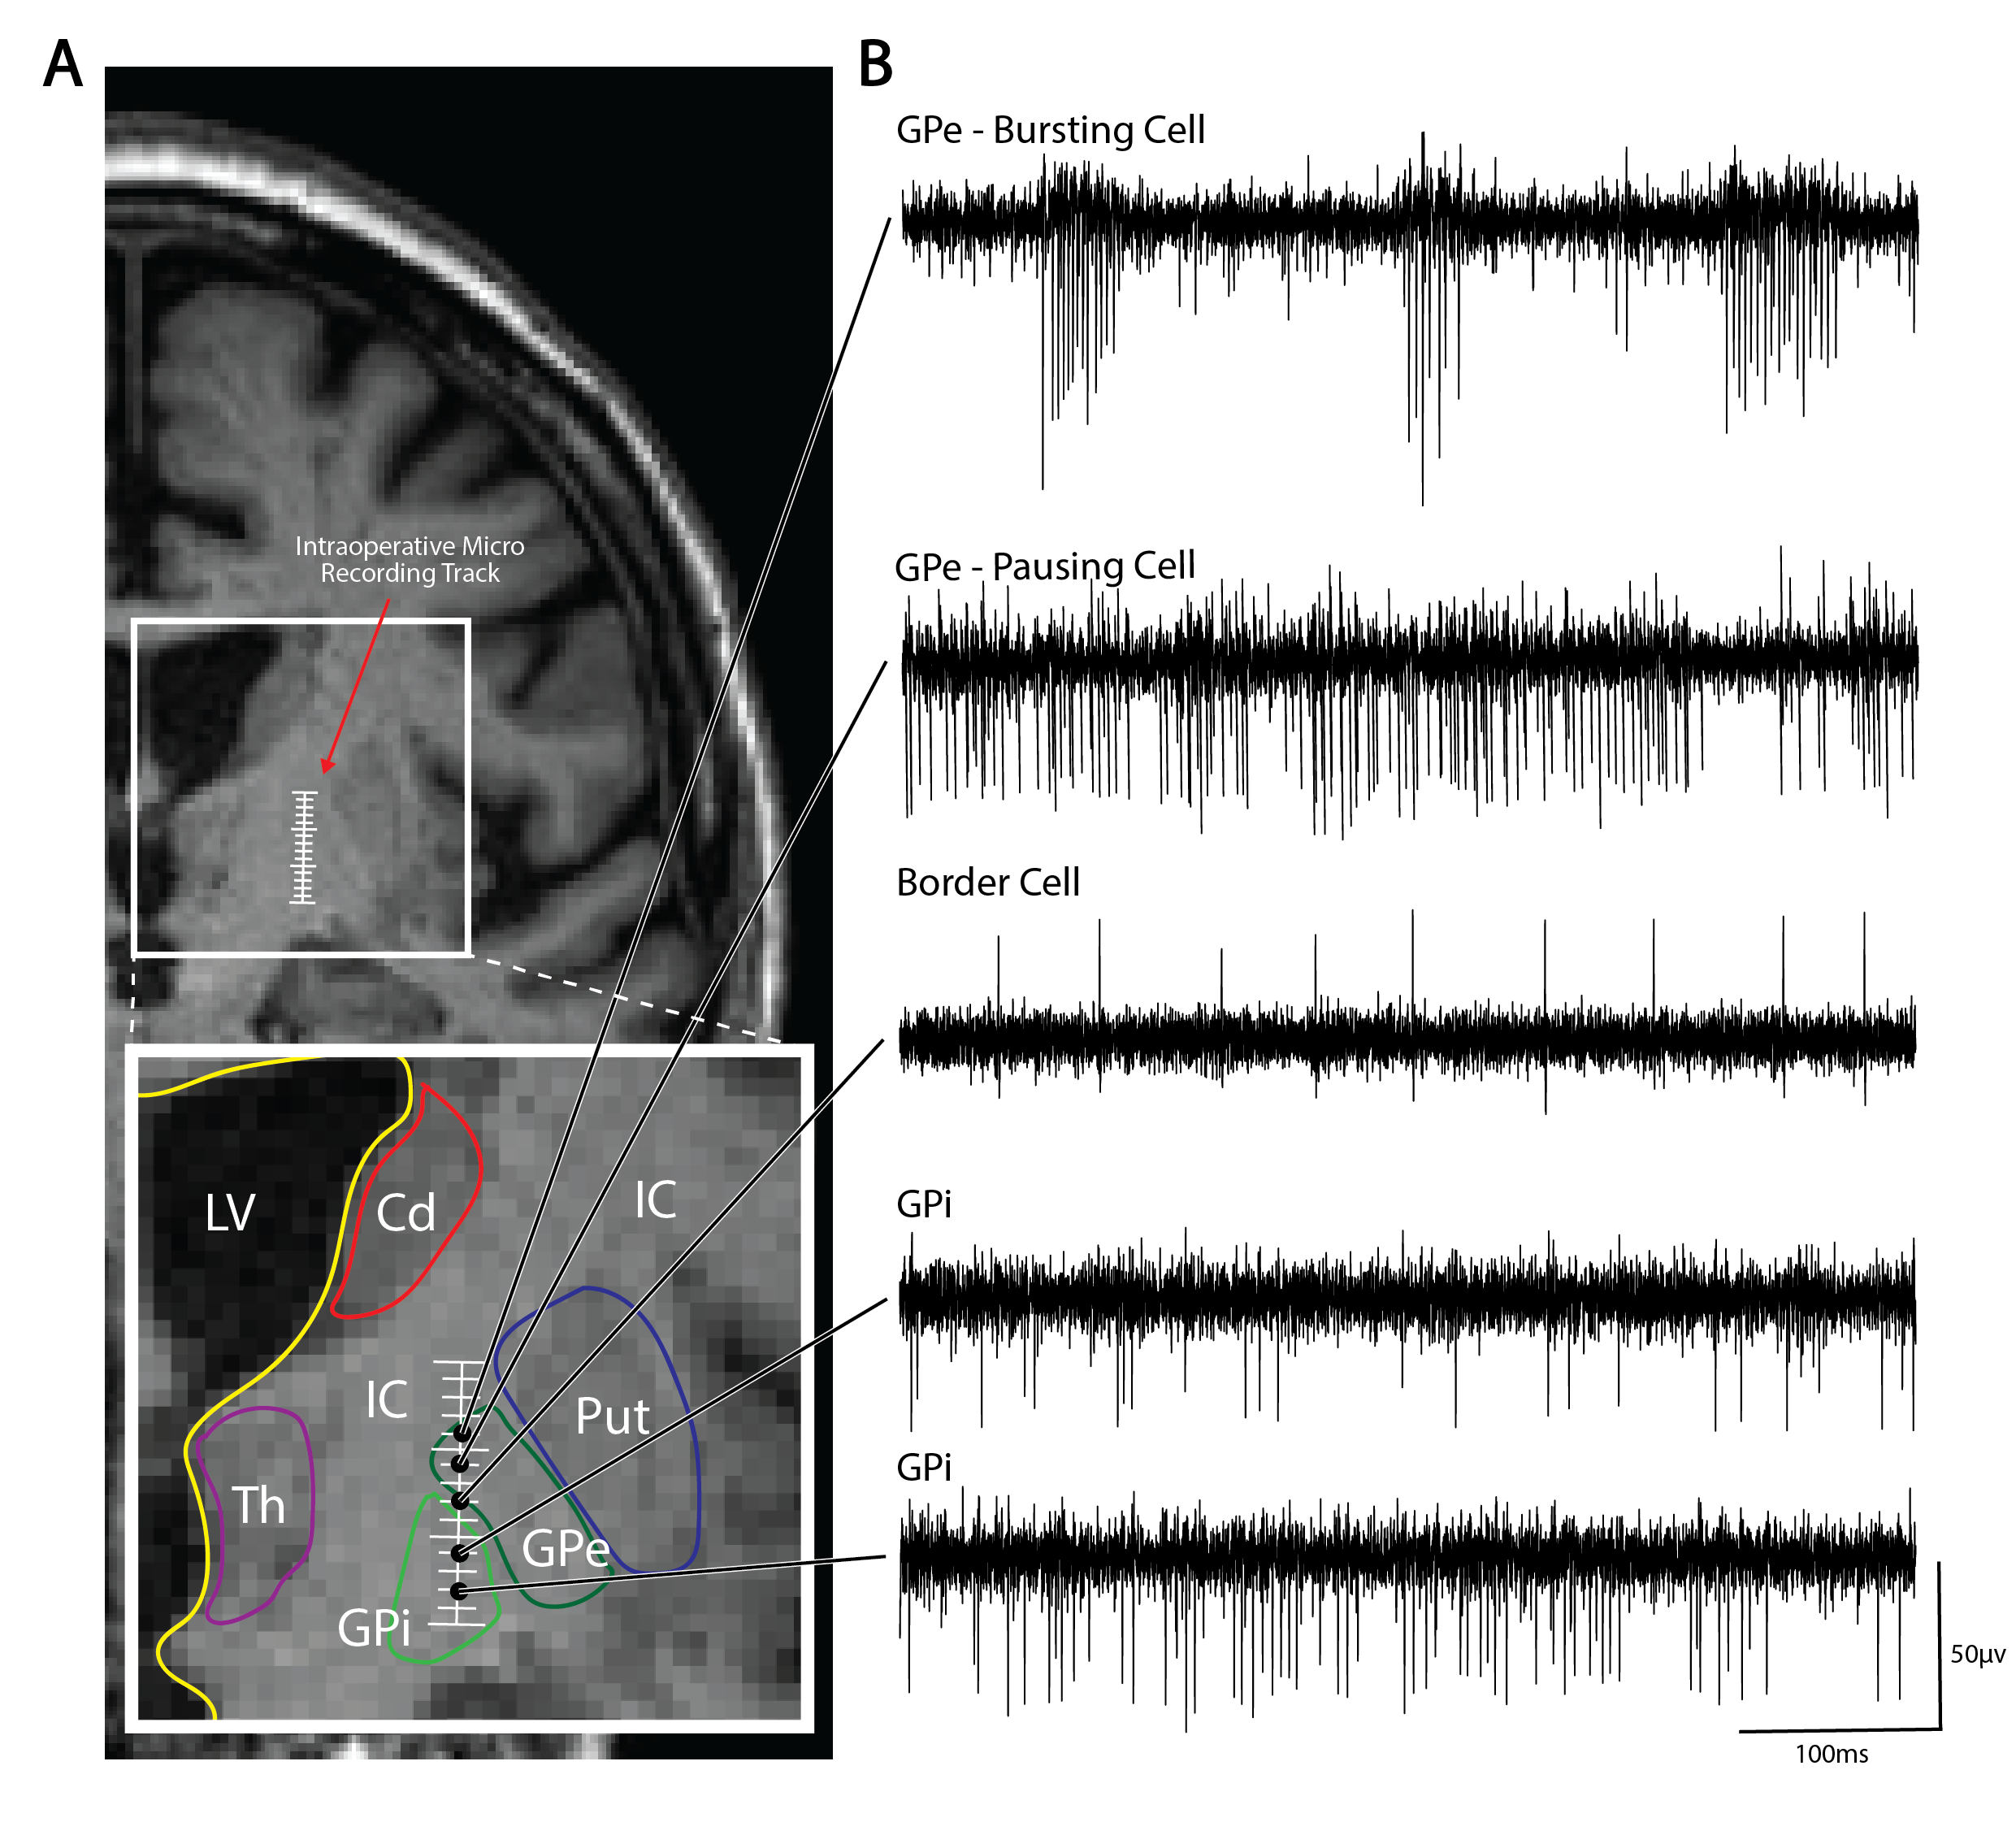

GPi DBS microelectrode recordings.

Typical ‘cell-types’ on GPi MER